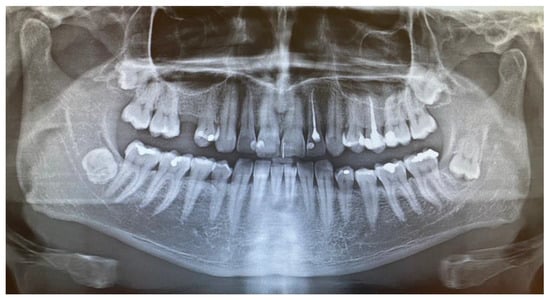

A 40-year-old patient was referred from a local dental office because of soft swelling in the right mandibular retromolar area. The lesion slowly grew over a long period, was symptomless, and was evaluated in time as a part of the swollen gums or pericoronal tissue enlargement overlying the impacted right mandibular wisdom teeth (Figure 1). Since the tissue had enlarged in time without any pericoronitis, inflammation, or changes in the bone area surrounding the impacted third molar, the patient was scheduled for consultation only because of the following atypical features of the lesion.

The patient was a generally healthy male without any history of surgery, illness, or surgery in the oral cavity region. The occurrence time of this lesion and its growth duration were not established. All of the surrounding anatomical areas and spaces were free of any diseases. Routine panoramic radiography (panx) and cone-beam computed tomography (CBCT) excluded any major changes in the bone near the tumour and excluded any potential odontogenic cause of the MRT swelling. The cortical parts of the bone in the CBCT study were also normal. No bone erosions, infiltrations, tooth resorptions, or bone swelling were detected (Figure 3). Because of the lack of substantial bone involvement, except for the impacted right mandibular wisdom molar with visible signs of bone ankylosis, suspicion of a nonodontogenic tumour was established.

Figure 1. Preoperative panx (panoramic radiograph) showing four fully visible retained wisdom teeth (18, 28, 38, 48) and no osteolytic changes in the right retromolar mandibular trigone. The impacted left mandibular wisdom teeth had a visible follicular-like cyst appearance surrounding the crown; the fully retained right wisdom teeth are fully embedded in the bone in an ankylotic-like manner, without any cysts, in direct proximity to the inferior alveolar nerve.